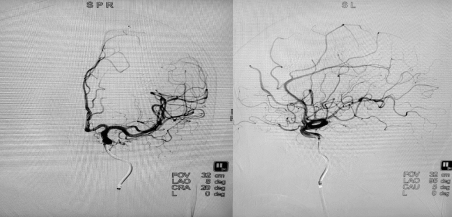

完全栓塞术后DSA

在罗有才副主任医师、李涛副主任医师、赵乐副主任医师、郭谢凡主治医师配合下,历时1小时余,成功治愈性栓塞了脑动静脉畸形。因患者颅内出血量大,又行脑内血肿钻孔引流术。术后患者恢复良好,与发病前无明显差别,对以后生活无明显影响,目前已康复出院。